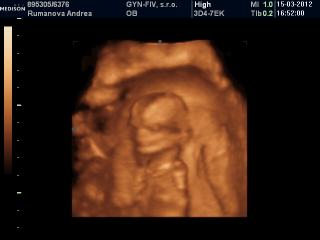

@andrea_stella jemine to je jake mrnave ja som to este veru nevidela taketo male na 4D 😀 😀 😀 nema chybu martanko maly resp. martanka tak by si to chcela ze 😀 😀 😀